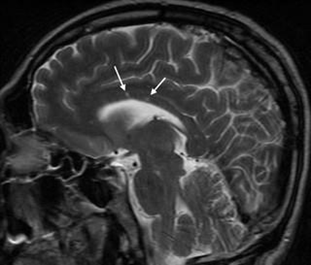

At the beginning of the 2018 temporal upper quadrantanopia, OD was presented. Because of the affection in several parts of the central neural system (CNS) and lesions in the corpus callosum (CC) in MRI, the patient was diagnosed as multiple sclerosis (MS). The neurological exam finds no abnormalities except for visual and hearing problems. The spinal fluid test of oligoclonal antibodies was negative, also as an infection test. Visual evoked potentials were normal. Because of the classical tirade of symptoms, we thought about possible SS. Repeated MRI showed “snowball” lesions in the CC (Figure 1).

Figure 1 MRI brain, case 1: sagittal T2 sequence, showing multiple hyperintense lesions in the CC (arrows).

The hallmark callosal lesion in SS is the “snowball” lesion as the appearance resembles a snowball on sagittal T2 and FLAIR sequences (as you can see in our patients' MRI). These likely pathognomonic lesions of SS are small (3–7 mm) and multifocal, involving the central fibers of the CC with relative sparing of the periphery.1 They represent microinfarctions due to occlusion of small precapillary arterioles consistent with the microvascular blood supply of the CC. The roof of the CC is more commonly affected, with microinfarcts taking on “icicle” and “spoke” configurations (Figure 3). It is important to note that MRI lesions in SS can disappear in comparison to MS lesions (Figure 5).